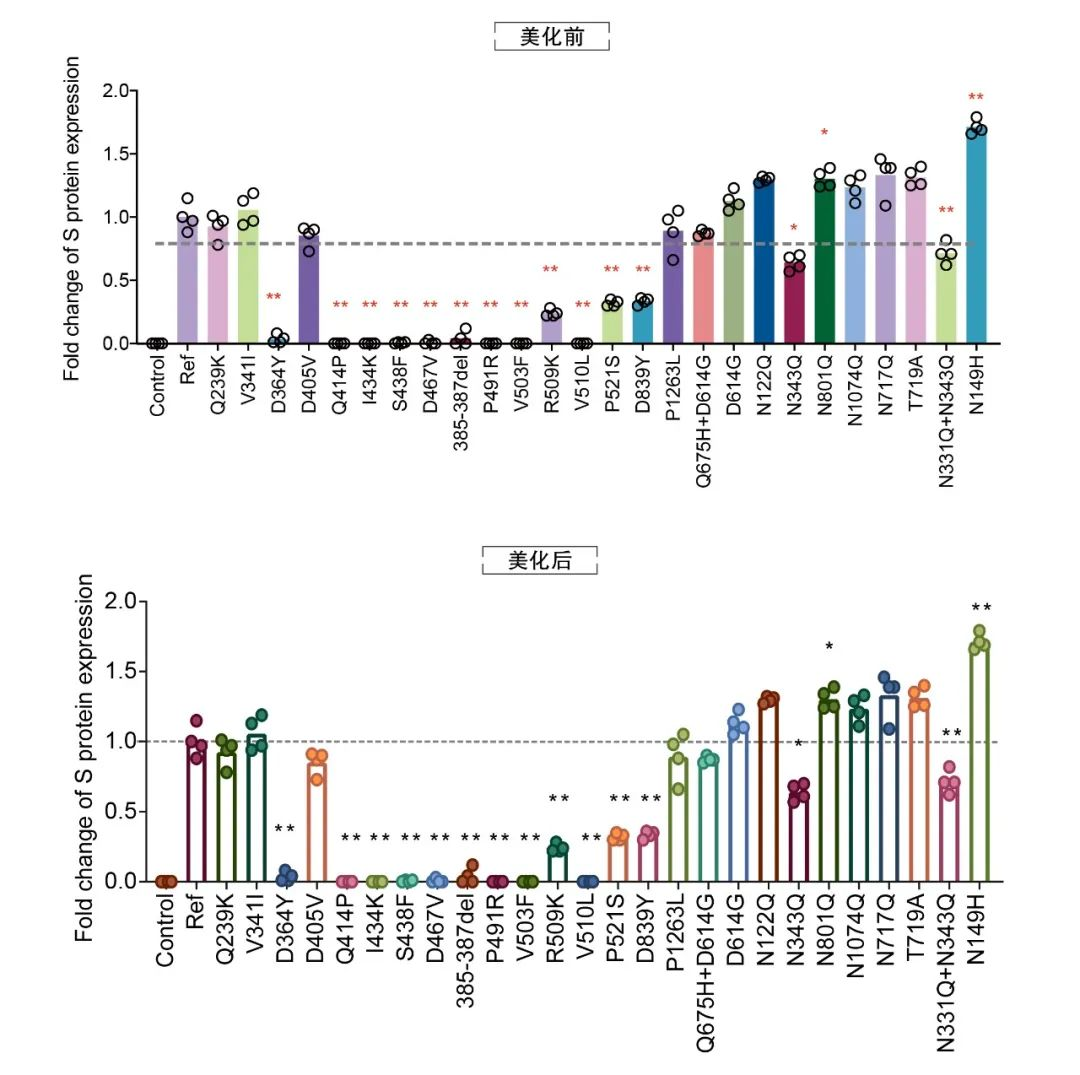

论文图表美化

滑动查看更多 点击查看大图